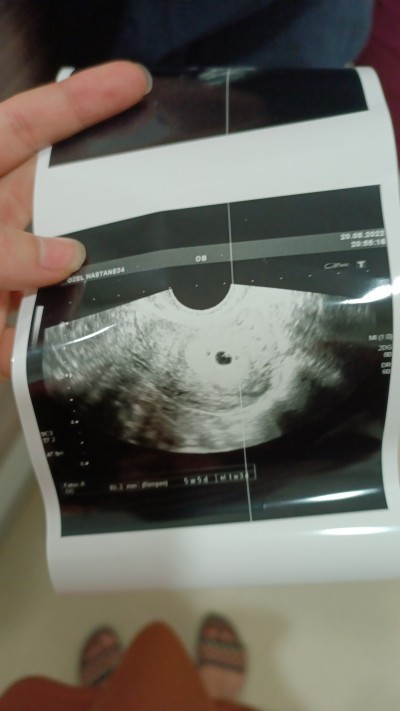

Kizlar dun kesemizi gordum bi tahminleri alabilirmiyim sizce kizmi erkekmi cok merak ediyorum keseden anlayanlari gordumde cok kucuk bide normalmi 5 hafta

Kese şekli değişkenlik gösterir 10.haftada benimki daha farklıydı belki o zaman tahmin yapılabilir şuan çok çok erken

Kesenin ortasındaki ne cnm kenarındaki anlayamadım benimde kesem böyle ama daha bebiş var yok demedi doktor